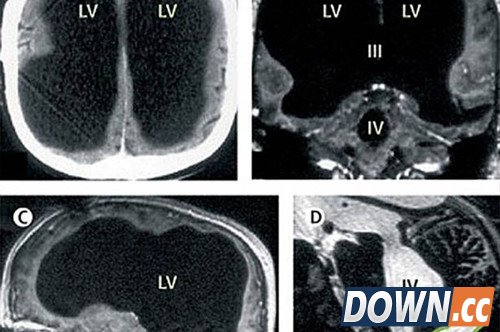

法国一名男子曾因腿部疼痛去医院检查,医生却找不出病根。在对其进行了全身体检后才发现,原来这名男子的腿疼是由脑部病变引起的,而该男子的大脑只剩下正常人大脑体积的一半都不到了。

报道称,这件事其实发生在2007年,近日由著名医学杂志《柳叶刀》披露。这名大脑神秘消失的男子当年44岁,医生在对其进行脑部检查后发现,他左右半脑上的额叶、顶叶、颞叶及枕叶都萎缩了。

医生指出,萎缩的这些部分是控制人类运动、感觉、语言、视觉、听觉、情感及认知能力的部分。

在对这名男子的病史进行详细调查后发现,原来他童年时患有后天脑积水症。但在他14岁时,经历了分流术,随后的30年,这名男子和家人都以为完全康复了。但其实他的大脑还是在病变,最终,脑内的积水损坏了脑组织,导致其大脑50%至75%的部分都消失了。

在经过了8年的研究后,科学家认为,人类的大脑其实有自我重组功能。也就是说,如果有部分脑组织死亡,其他部分会接替已死亡部分的能力和功能,并维持人体正常活动。